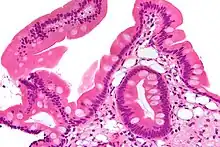

Low magnification micrograph of Whipple's disease showing the characteristic foamy appearing infiltrate of the lamina propria. Duodenal biopsy. H&E stain. | |

Endoscopy of the duodenum and jejunum can reveal pale yellow shaggy mucosa with erythematous eroded patches in patients with classic intestinal Whipple's disease, and small bowel X-rays may show some thickened folds. Other pathological findings may include enlarged mesenteric lymph nodes, hypercellularity of lamina propria with "foamy macrophages", and a concurrent decreased number of lymphocytes and plasma cells, per high power field view of the biopsy.